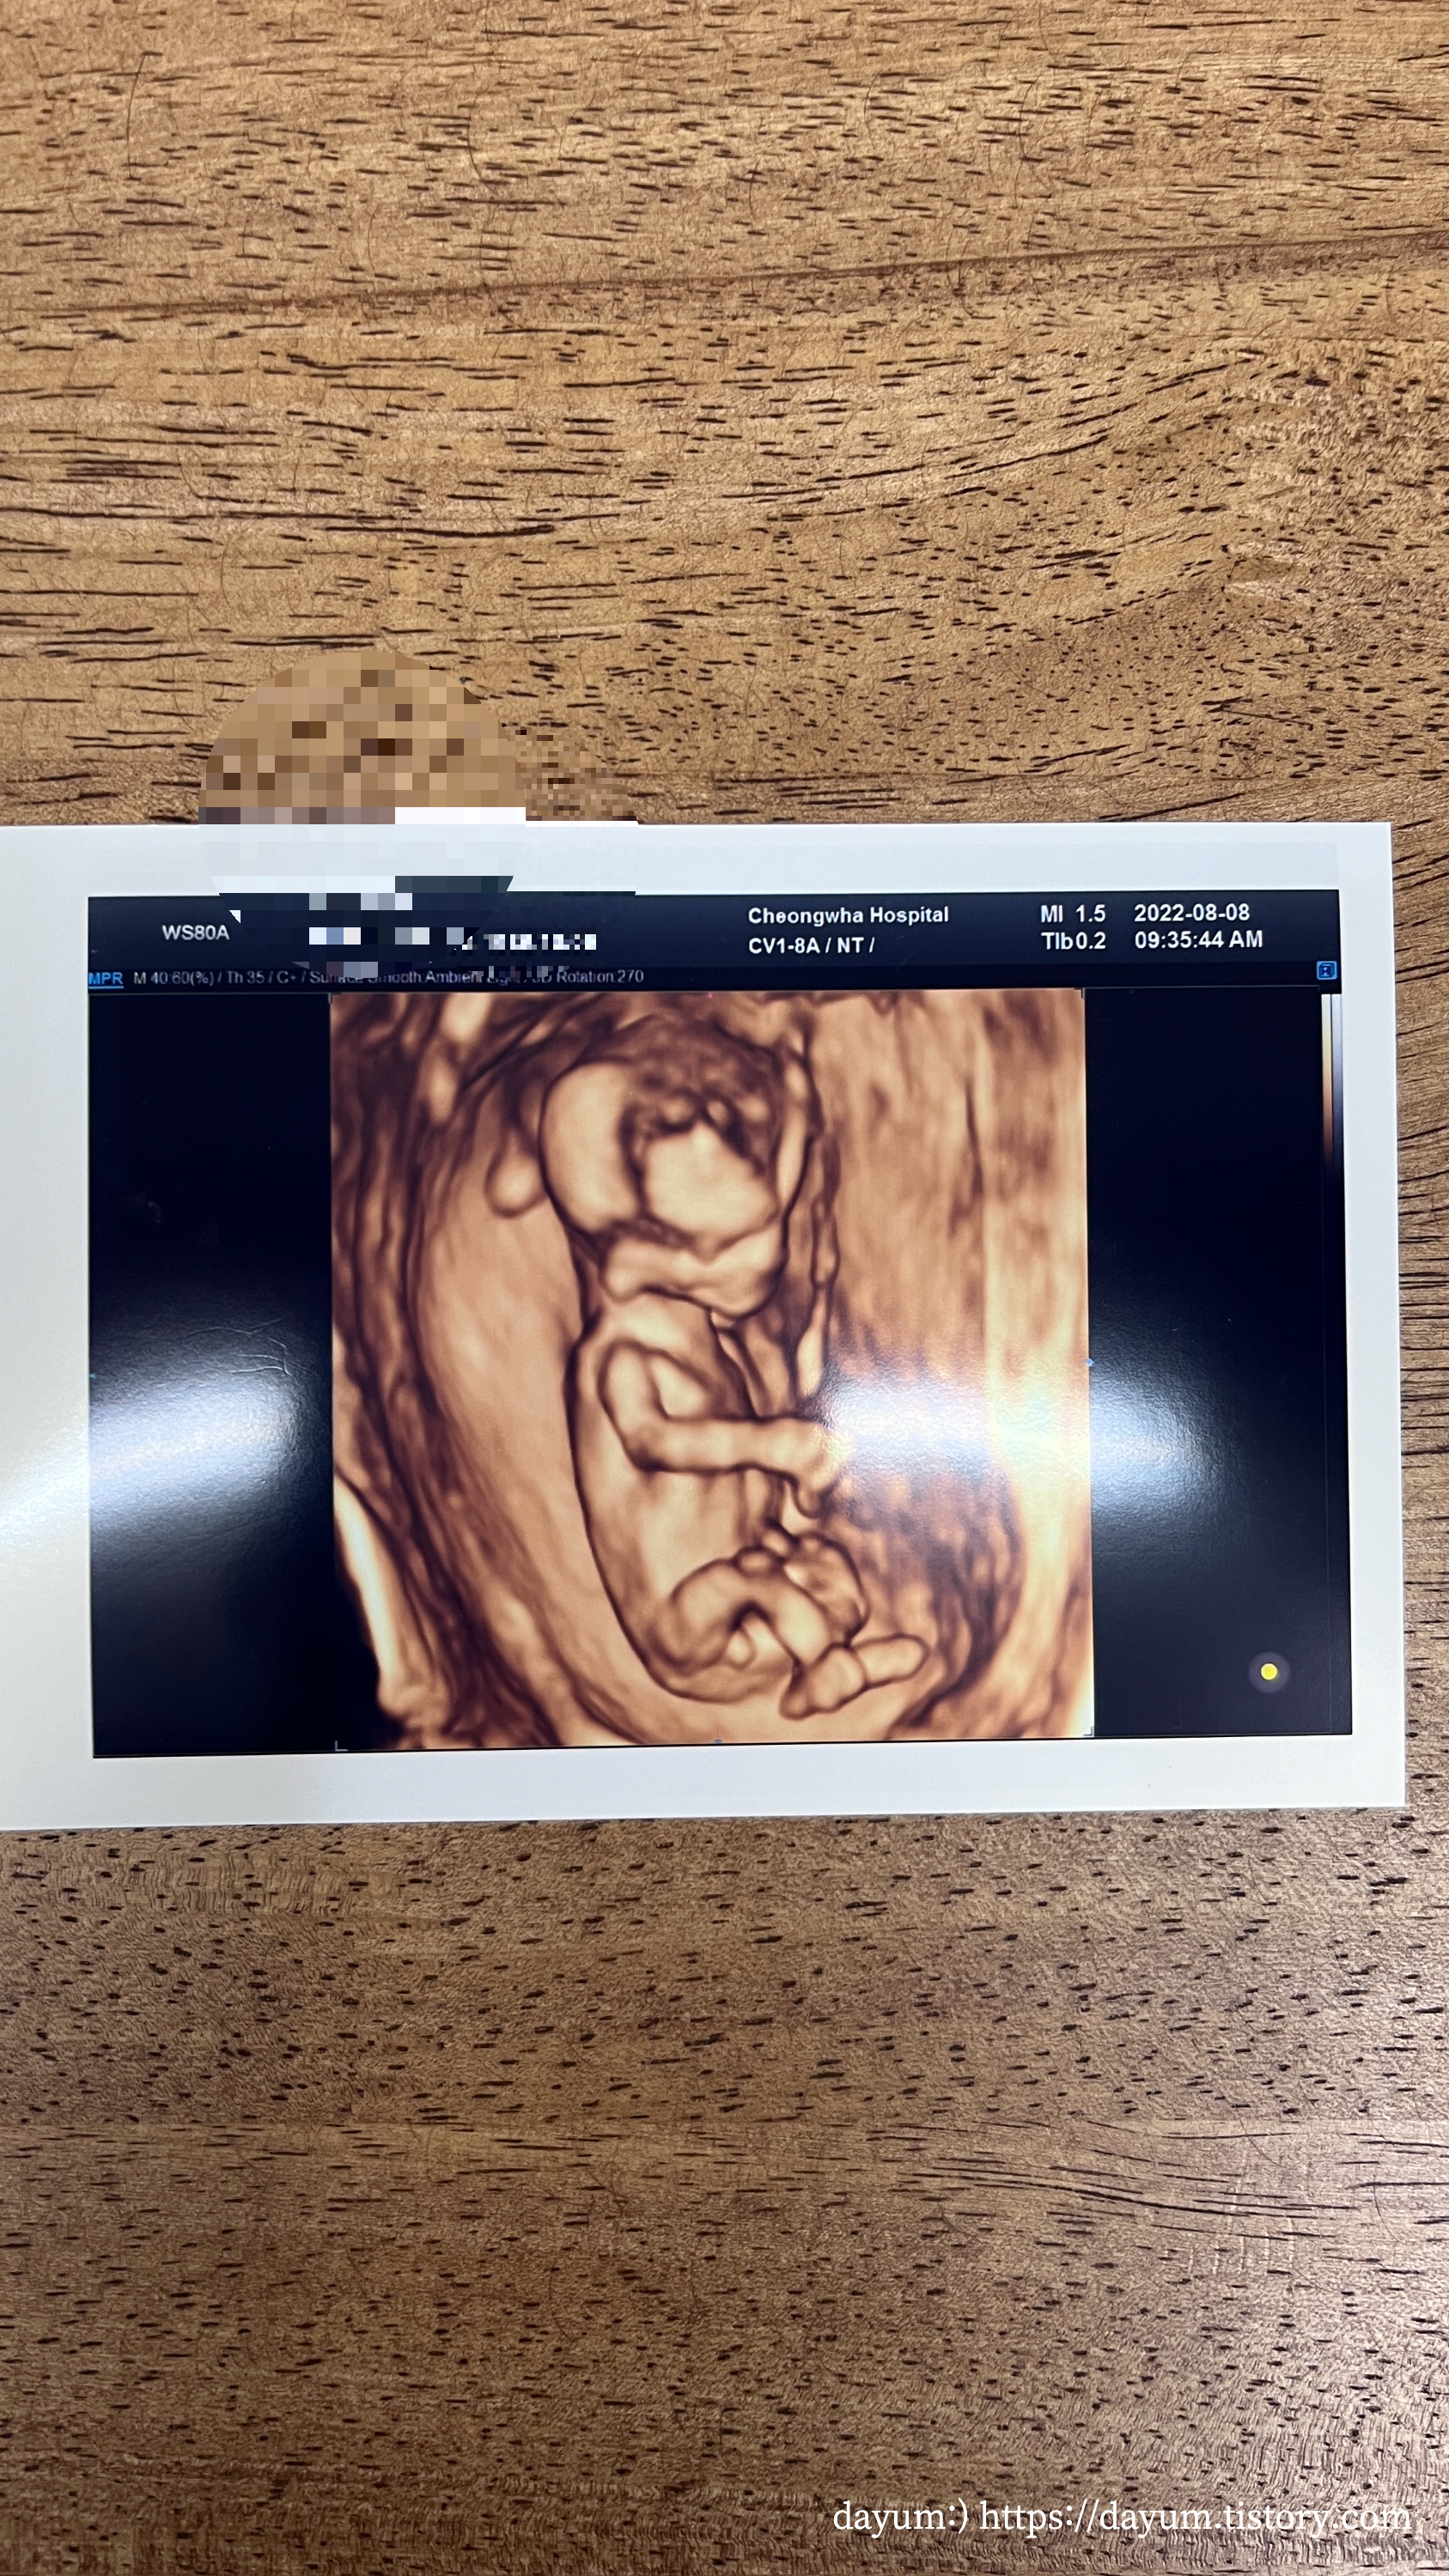

우리 부부는 처음부터 니프티를 하기로 마음을 먹었기 때문에 입체초음파를 보고 목투명대검사를 했다.

입체초음파는 태아가 협조를 잘 해줘야 금방 끝난다고 했는데 조이는 잘 자고 있다가 끝날 때 쯤 일어나서 약 7분만에 끝났다.

진료실에는 남편 출입불가였는데 입체초음파실에는 같이 봐도 된다고 하셔서 같이 봤다.

너무 귀엽고 뭉클하고, 같이 봐서 기쁨이 더 했다.

생각보다 배꼽 아래에 있었는데, 두다리를 꼬고 있고, 한쪽 팔로 가드를 치고 있었다.

태아의 뇌는 나비모양으로 잘 형성되었고, 코뼈, 상악, 하악 모두 잘 만들어졌다고 한다.

탯줄로 혈액이 공급되는 것도 봤고 목투명대는 1.31mm로 정상범위에 있다고 한다.

입체초음파가 끝나고 원장님과 다시 한번 보면서 아기의 머리에서 엉덩이 까지의 길이, 머리 크기 등등 다시 설명을 듣고 더맘스캐닝플러스 신청서를 작성했다. 더맘스캐닝은 60만원 더맘스캐닝플러스는 75만원인데 검사할 수 있는 종류는 각각10가지, 126가지라서 이왕하는거 플러스로 선택했다.